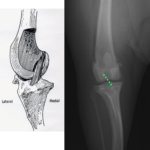

【症例紹介】前十字靭帯損傷

【症例紹介】膝蓋骨脱臼と前十字靭帯断裂(TPLO)

【症例紹介】手根脱臼(関節固定)

【症例紹介】前十字靭帯損傷(TPLO)